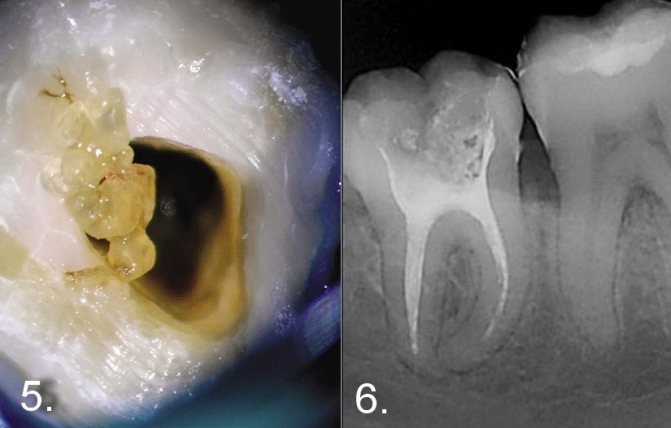

Удаление нерва зуба является классическим методом лечения пульпита. Его суть заключается в проведении следующих этапов –

- высверливание всех пораженных кариесом тканей (рис.2),

- удаление пульпы зуба (проводится при помощи специального инструмента),

- механическое расширение каналов (рис.3),

- пломбирование каналов корня зуба (рис.4),

- пломбирование коронковой части куба (рис.5).

Лечение пульпита: этапы депульпирования зуба

Ниже мы более подробно распишем каждый этап лечения пульпита, возможно, эта информация поможет вам выявить горе-стоматолога, и предупредить некачественное лечение и его осложнения.

Второе посещение:

- Удаление временной пломбы.

- Промывание каналов антисептиками.

- Рентгенологический контроль пломбирования (обязателено!!!) если на рентгене все Ок – приступаем к следующему этапу. Но, если видим, что канал недопломбирован до верхушки, либо гуттаперчевые штифты выходят за пределы корня в окружающие ткани – необходимо удалить все гуттаперчевые штифты и начать пломбирование каналов сначала. На рис.17-19 вы можете увидеть качественно запломбированные корневые каналы (все корневые каналы запломбированы до верхушки корня). К сожалению стоит отметить, что подавляющее большинство стоматологов если и видят, что корневые каналы запломбированы – работу не переделывают. Именно с этим и связан озвученный нами в начале статьи процент некачественного лечения пульпита (в 60-70% случаев). Вид качественно запломбированных корневых каналов –

В конце посещения ставится временная пломба, а пациента предупреждаем, что зуб может начать болеть после прохождения анестезии. Помочь снять боль помогут хорошие таблетированные анальгетики. Небольшая боль является нормой, т.к. при инструментальной работе в каналах К-файлы немного травмируют ткани в области верхушки корня.